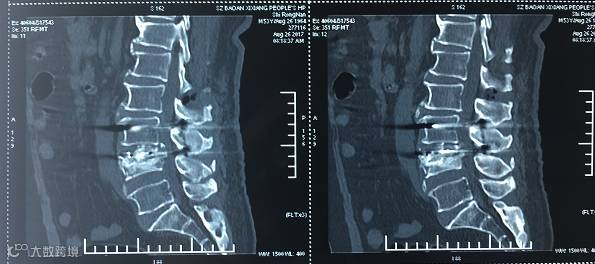

【术前CT】